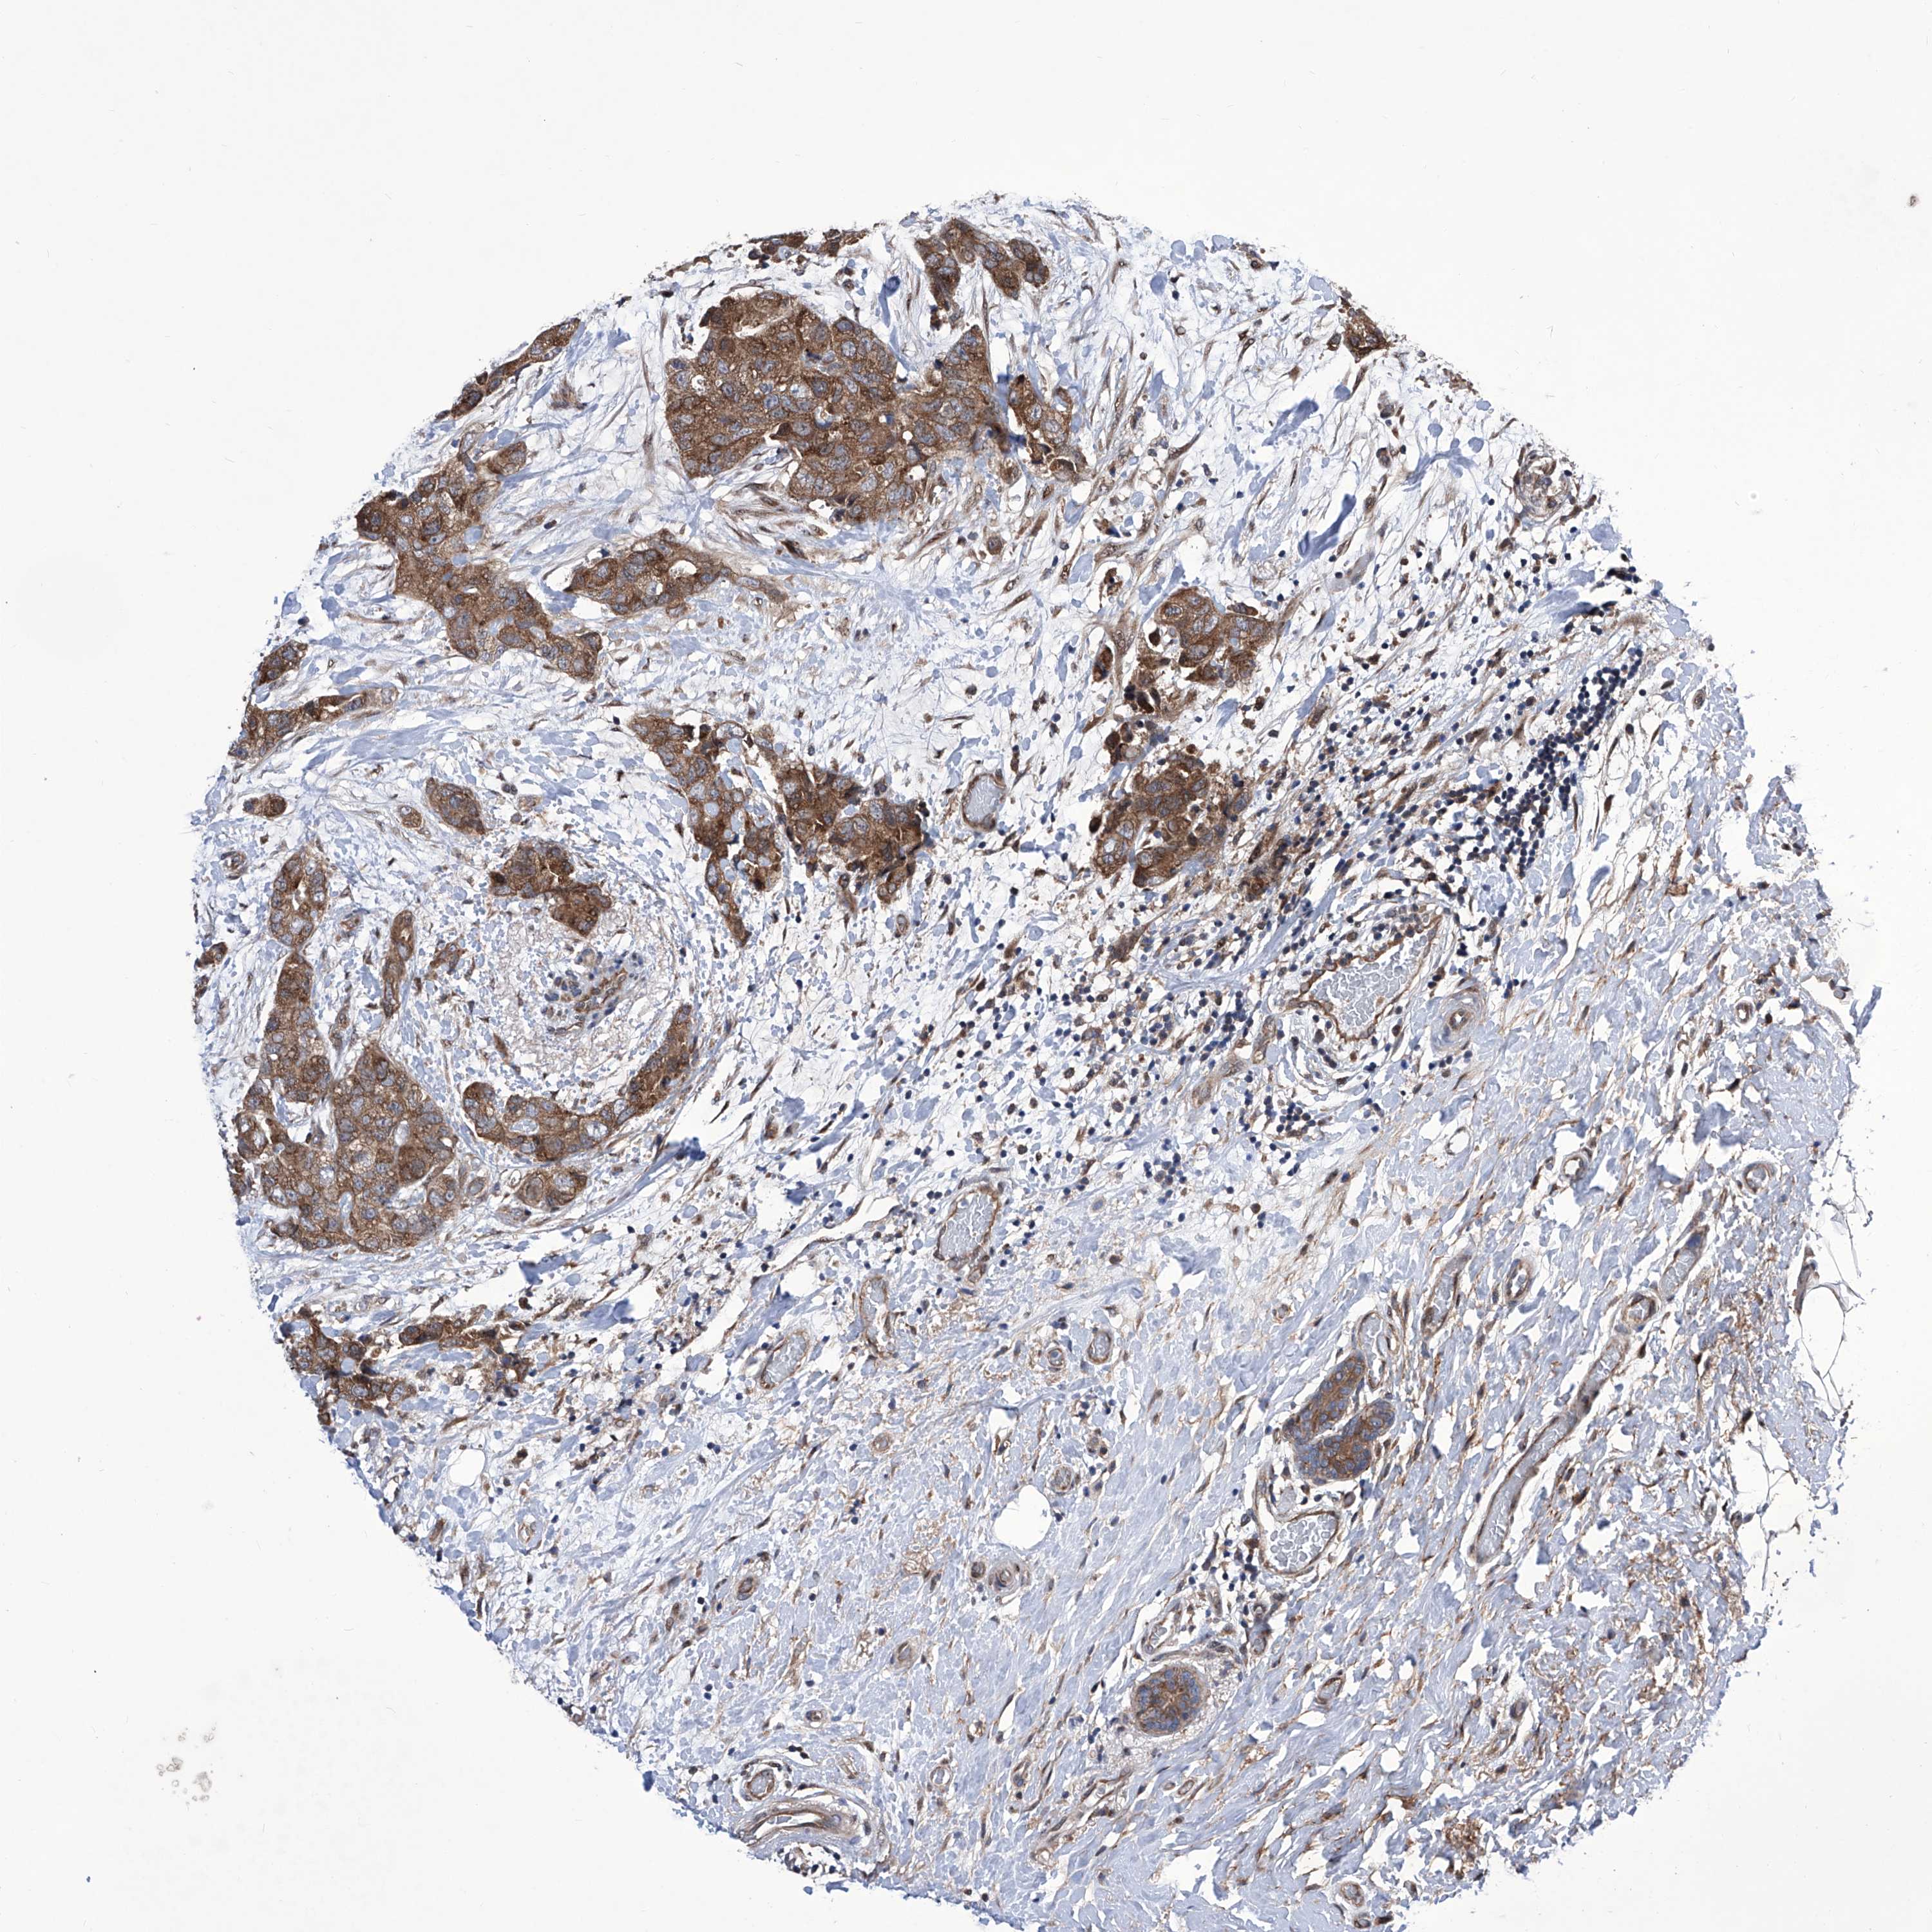

CANCER BREAST CANCER Show tissue menu

BRCA TCGA BRCA VALIDATION PROTEIN EXPRESSION